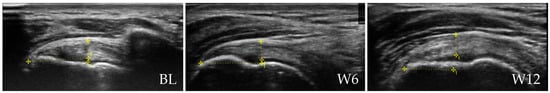

Figure 4 presents representative ultrasound images of the ST of a patient from the rESWT group at BL, W6 and W12.

Representative ultrasound images of the supraspinatus tendon (ST) of a patient in the rESWT group at baseline (BL), 6 weeks (W6) and 12 weeks (W12) post-baseline. ST thickness measurements are indicated by vertical lines (5.7 mm at BL, 5.1 mm at W6 and 5.1 mm at W12). All patient-identifying information has been removed to protect privacy.